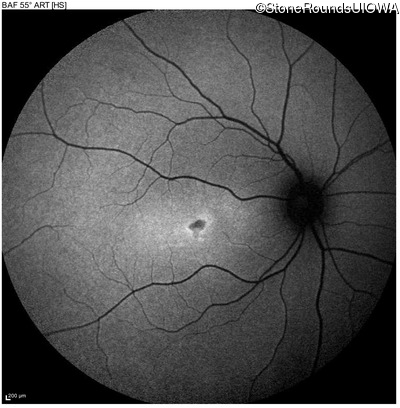

Age at visit: 17 years

OD OS

This 17 year old female first noted problems with her visual acuity around age 13 when she had trouble seeing the projector from the back of the classroom.

Age at visit: 16 years

Age at visit: 18 years

Age at visit: 22 years